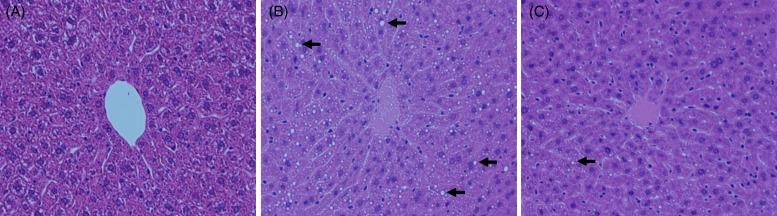

Turmeric () is a widely used spice that has various biological effects, and aqueous extracts of turmeric exhibit potent antioxidant activity and anti-inflammatory activity. Bisacurone, a component of turmeric extract, is known to have similar effects. Oxidative stress and inflammatory cytokines play an important role in ethanol-induced liver injury. This study was performed to evaluate the influence of a hot water extract of (WEC) or bisacurone on acute ethanol-induced liver injury. C57BL/6 mice were orally administered WEC (20 mg/kg body weight; BW) or bisacurone (60 µg/kg BW) at 30 min before a single dose of ethanol was given by oral administration (3·0 g/kg BW). Plasma levels of aspartate aminotransferase and alanine aminotransferase were markedly increased in ethanol-treated mice, while the increase of these enzymes was significantly suppressed by prior administration of WEC. The increase of alanine aminotransferase was also significantly suppressed by pretreatment with bisacurone. Compared with control mice, animals given WEC had higher hepatic tissue levels of superoxide dismutase and glutathione, as well as lower hepatic tissue levels of thiobarbituric acid-reactive substances, TNF-α protein and IL-6 mRNA. These results suggest that oral administration of WEC may have a protective effect against ethanol-induced liver injury by suppressing hepatic oxidation and inflammation, at least partly through the effects of bisacurone.

摘要